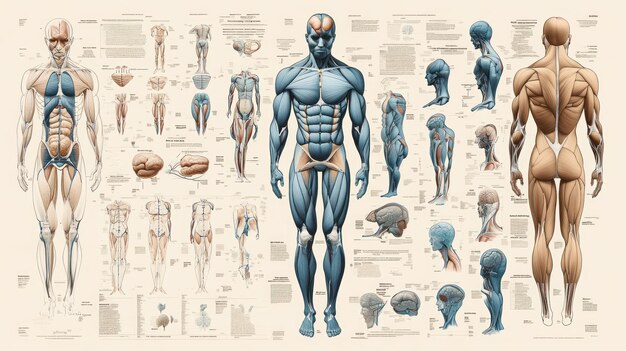

Human Anatomy Chart Showing Muscle And Skeletal Sy 412938257

14/11/2025

ร่างกายมนุษย์